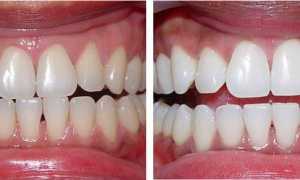

- Прорезывание зубов — часто при неправильном прорезывании зубов (как правило, встречается у детей) на десне (над зубом или под ним) формируется небольшой костный нарост розового или белого оттенка. Иногда появление шишки сопровождается болью, припухлостью десны и повышением температуры тела, а иногда просто лёгким дискомфортом при разговоре или во время еды. Основной причиной подобного явления служит аномальное формирование зуба (растёт не в том направлении).

Фото 1. Шишка на верхней десне у ребенка, при прорезывании молочных зубов.